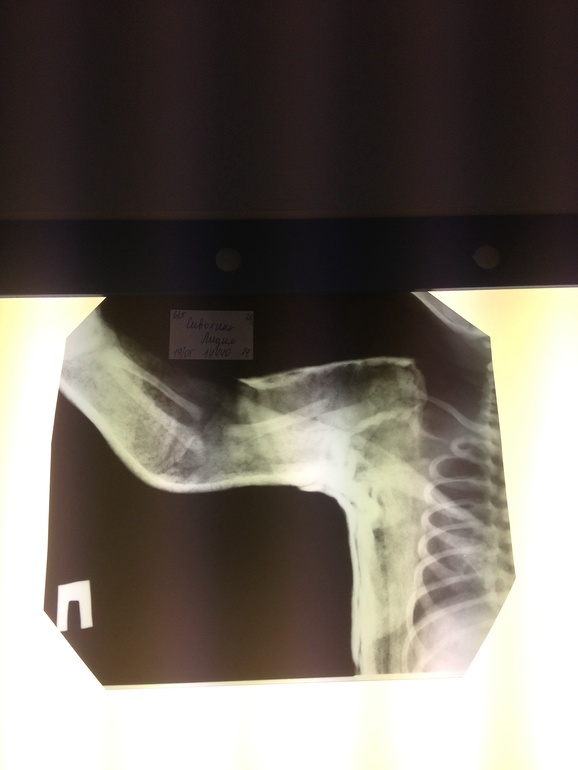

Да не так уж и много смотрю и 5 рожают при чем сами и норма, а у нам 4740 и 58 кг. Многие говорили в суд, но понятно врачи всегда друг друга прикроют, а я только время потеряю, у меня трое деток и надо ими заниматься, и Лидушке за свой счет по массажам бегала ручку разрабатывала, после гипса как плеть висела, так боялась последствий, Бог миловал все обошлось, были бы последствия начала бы судится

Лапонька! Это при плановом кесаревом как можно было умудриться сломать ручку ребенку?

Сама понять не могу, вообще не ждала подвоха, одна отговорка крупная, это вы легко отделались мы могли бы потянуть за шею и последствия были бы плачевнее...,как то так. Виновата сама нечего было ее так раскармливать, а мои объяснение что у меня предрасположенность к крупным плодам при моем росте 180, ответ Ваши проблемы